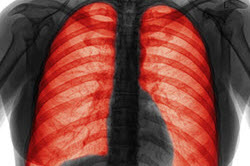

什么是慢性阻塞性肺病?

慢性阻塞性肺病或COPD是指一組導致氣流阻塞和呼吸相關問題的疾病。它包括肺氣腫和慢性支氣管炎。